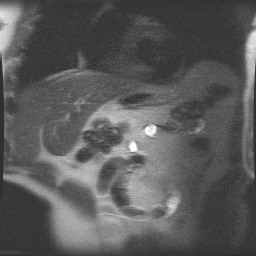

Abdomen